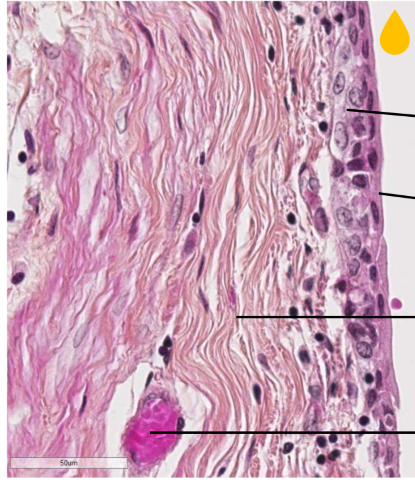

Voici une coloration spéciale papanicolaou, indique quel type de cell est indiqué par les flèches et quel colorant est utilisé

A

Noyau coloré par hematoxyline

Cellules intermédiaires colorées par vert lumière

Cellules superficielles (plus grosses) colorées par l’éosine